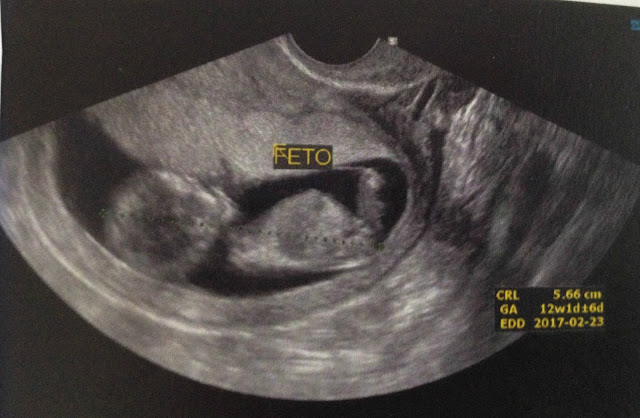

Com 12 semanas é quando se faz à Translucência nucal um exame bem importante que pode detecta anomalias e doenças no bebê, confesso que fiquei alguns dias sem dormir por conta desse exame, mas graças à Deus tudo correu bem, nesse exame o médico também consegue dar um chute sobre o sexo, isso se você já não fez a sexagem fetal e acabou com sua ansiedade.

Nós optamos por não fazer, acho que todo esse sentimento de que minha ficha ainda não caiu sobre eu estar de fato grávida me fez não ser tão ansiosa quanto eu achei que seria, não me arrependo nem um pouco de não ter feito o exame, o médico deu um chute no exame da TN de que seria um menino,e é o Santiago óbvio ficou em êxtase, eu idem pois sempre quis fosse menino.